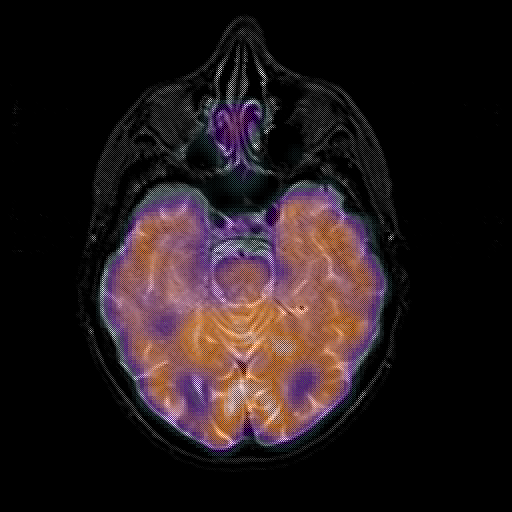

overlay 1: Slice 19

Slice 19

MRCBFCBF with

T1PDT2T1PDT2